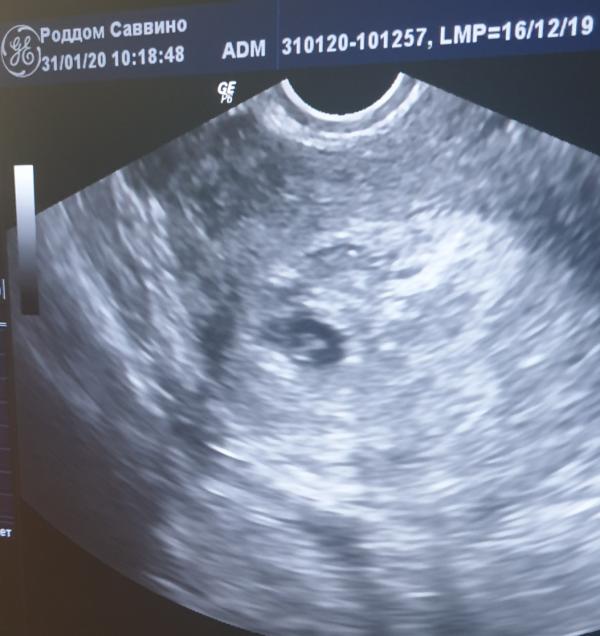

Печально, конечно ........ осознавать, что ты сделала, всё что было возможно, но видно как Богу угодно🙏🤦🏻♀️ Поступила в четверг 30.01, с мажущими выделениями (дома розового, в больнице уже коричневого цвета). На следующий день кровь, моча, уколы, таблетки, УЗИ ( плодное яйцо 12мм, эмбрион вроде есть,но плохо визуализируется, он к слову сказать расположен в верхнем правом углу матки и узистка,нервно водила датчиком о все время орала....ничего не вижу....нет чёткости.....не вижу....давила на живот сверху,чтобы он как то отразился в датчике🙄🤦🏻♀️потом опять орала не вижу.....) с этими словами, меня оставили в роддоме до понедельника,сказав что по сроку уже должно быть чёткое очертание эмбриона, пусть и пока без сердцебиения, которое тоже уже должно быть 🤔 назначили контрольное узи на понедельник. Между тем,мазня никак не собиралась проходить, могло пол дня быть чисто, а потом под вечер мазнуть алым пятном, после которого начиналась коричневая мазня,к слову это происходило раз в 2 дня и имело какую-то цикличность, я знала,что сейчас почти закончилось....жди новый мазок🤦🏻♀️✌так и было. В понедельник делала узи,всё таже орущая невростичка, она даже толком не смогла ничего изменить, сказала лишь, что размеры плодного яйца такие же, эмбрион не визуализируется, серцебиения нет, плодное яйцо деформировано.......диагноз..... неразвивающаяся беременность👏👏👏 рекомендована чистка с удалением плодного яйца из матки👏 врач предложила вакуум. Я написала отказ. Меня оставили в больнице на 3 дня, завтра еще одно контрольное узи, по результатам которого уже точно сомнений не будет видимо не у кого🤦🏻♀️ну конечно, я ищу положительные стороны в этой беременности, но блядь с каждым днём 🤦🏻♀️головой понимаю, что дело труба🤦🏻♀️и видимо этому малышу не суждено родиться в нашей семье 🙏от этого мне ещё хуже и морально и физически, я уже реально очень истощена,не хочу никого не видеть, не слышать, не говорить🤦🏻♀️😰 Ну и что я имею...... Мазня не проходит, дюфастон в лошадиной дозе уже🤦🏻♀️, 2 дня тянет и побаливает правый бок (а там как раз прикрипление), боли схваткообразные, хгч вчера взяли,но готово будет завтра (но на него врач сказала особо не полагаться,хгч при неразвивайке растёт нормально), эмбрион на таком сроке не видно, хотя должно быть👆 Муж сказал, держись, Бог даст,если получится может ещё родим🙏жалко,ну а что делать! Конечно я опять надеюсь на чудо,вдруг завтра 💗забьется,ну или в размерах подрастёт, или визуализация будет эмбриона🙏ну мало ли. Если нет, то вакуум🙏😥🤦🏻♀️ сил больше нет.

@ylua_mom2020 этот он был такой неделю назад, он должен как минимум расти хоть немного, он не растёт. На узи в понедельник его размеры были такие же, что и в пятницу, а так быть не модет и не должно